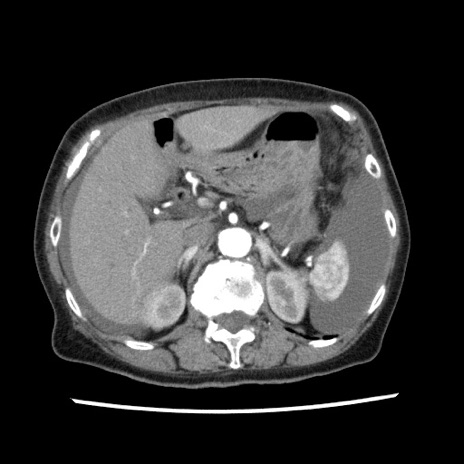

矢状断像

【症例】80歳代女性

【主訴】腹痛

【現病歴】8時間前から腹痛あり来院。

【既往歴】糖尿病、脂質異常症、子宮体癌にて子宮全摘術

【身体所見】意識清明・会話良好だが腹痛で苦悶様、全腹部にわたって反跳痛と圧痛あり

【データ】WBC 13600、CRP 0.14、LDH 224、CK 90